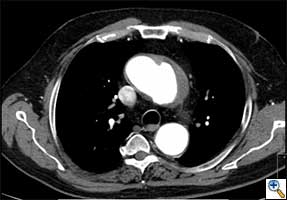

| FIGURE 1-3: 2D and 3D preoperative CT Images of a 78 year old man with aortic insufficiency, and ascending, arch and descending aortic aneurysm with mural thrombus. | |

Appropriate patients for this procedure have extensive thoracic aortic disease and a suitable landing zone for a stent graft in the descending aorta. Many of these patients are candidates for a 2-stage procedure, and selection is based on expected outcomes and the estimated interval rupture risk if patients were to be treated in a staged fashion. (see Figs. 1-3)

- Thorax CT angiogram with 3-D reconstruction, which is invaluable in the assessment of these patients. Attention must be paid to the detailed arch anatomy, taking note of any anomalies (eg. anomalous vertebral artery, bovine aortic arch), the diameter of the aorta distal to the LSCA, extent and diameter of the descending aorta aneurysm, and the diameter of the expected landing zone. Furthermore, the extent of atheroma/aortic calcification should be evaluated.